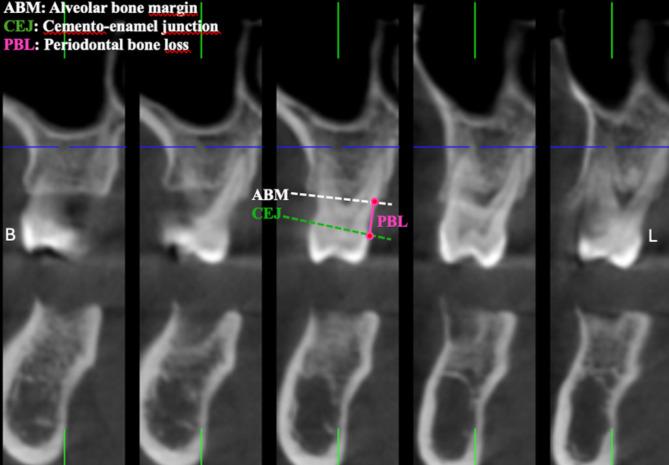

Nine hundred thirty-nine maxillary posterior segment images from 527 subjects were retrospectively scanned via CBCT. A total of 826 premolar, 701 first molar and 817 s molar teeth were examined. The maxillary sinuses in each segment were divided into anterior, median and posterior regions according to the tooth roots they were associated with, and their membrane thicknesses were measured and categorized. The effects of age and gender on membrane thickness were evaluated. T tests and one-way ANOVA were used to analyze differences between groups, followed by post hoc Tukey tests for multiple comparisons. Additionally, correlation analyses were performed to investigate the relationships between the categorized membrane thicknesses and periodontal bone loss.

A significant positive correlation was found between maxillary sinus membrane thickness and periodontal bone loss in all three regions (p < 0.05). Periodontal bone loss was greater in regions with class IV membrane thickness (p < 0.001). Sinus membrane thickness and periodontal bone loss were greater in men and older people (p < 0.001).

回顾性扫描了来自527名受试者的939张上颌后段图像。共检查了826颗前磨牙、701颗第一磨牙和817颗第二磨牙。每个节段的上颌窦根据与其相关的牙根分为前部、中部和后部区域,并测量其膜厚度并进行分类。评估年龄和性别对膜厚度的影响。使用t检验和单因素方差分析来分析组间差异,随后进行事后Tukey检验以进行多重比较。此外,进行相关性分析以研究分类后的膜厚度与牙周骨丧失之间的关系。

在所有三个区域中,上颌窦膜厚度与牙周骨丧失之间均发现显著正相关(p < 0.05)。IV类膜厚度区域的牙周骨丧失更大(p < 0.001)。男性和老年人的窦膜厚度和牙周骨丧失更大(p < 0.001)。